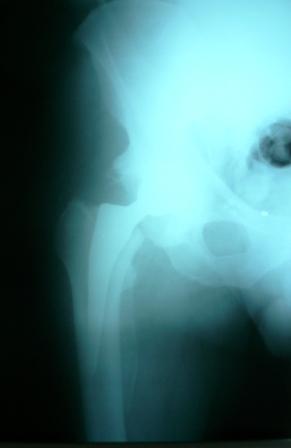

Больной Т. 56 лет, Диагноз: двухсторонний коксартроз 3-4 ст справа, 1-2 ст слева 2.10.08 выполнена операция тотальное бесцементное эндопротезирование. Использовался наружный доступ, положение на боку. Операция протекала без особенностей.

Выполнен послеоперационный ренгеноконтроль в прямой проекции